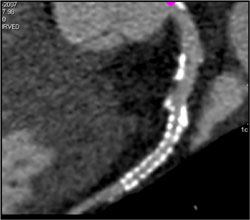

Patent LAD Stent